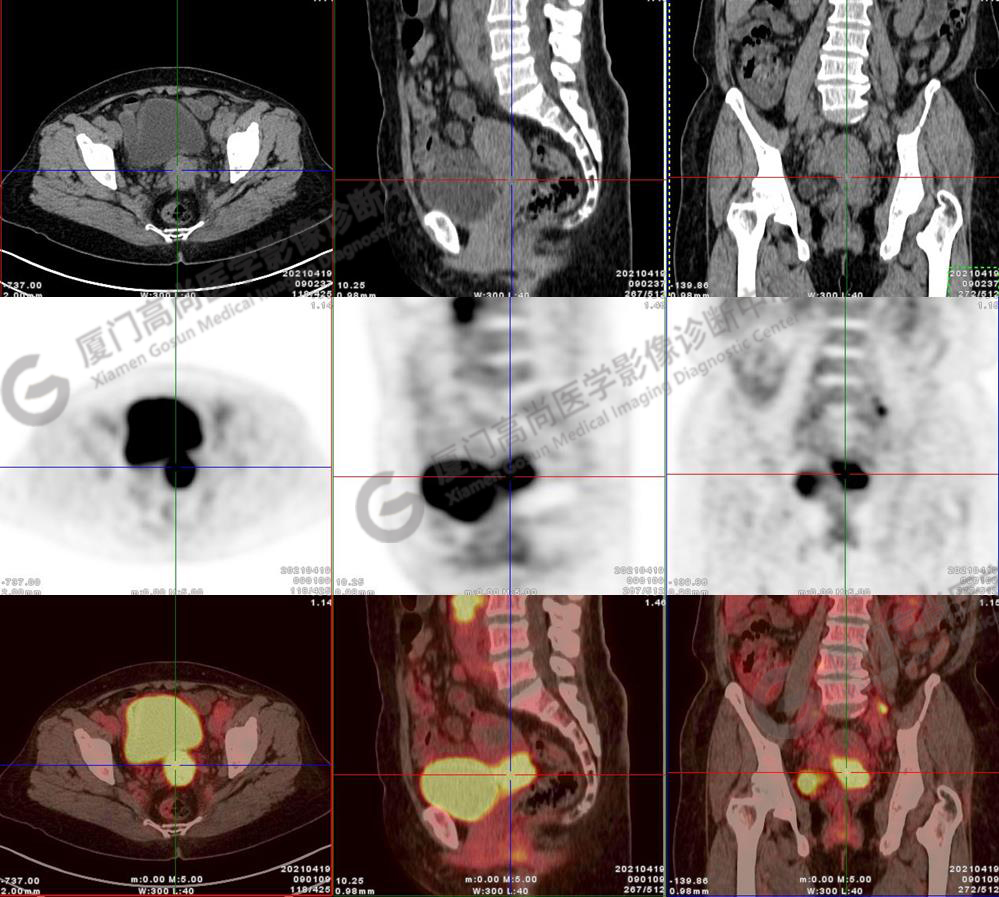

圖2-9:雙側(cè)鎖骨區(qū)、縱隔、右側(cè)內(nèi)乳區(qū)、腸系膜緣、腹膜后、雙側(cè)髂血管旁及盆腔多發(fā)腫大淋巴結(jié)影,代謝不同程度增高,考慮為轉(zhuǎn)移。

圖10-11:子宮頸軟組織腫塊,代謝異常增高,考慮為宮頸癌。

圖12-13:延遲2小時后,宮頸腫塊糖代謝進一步增高。